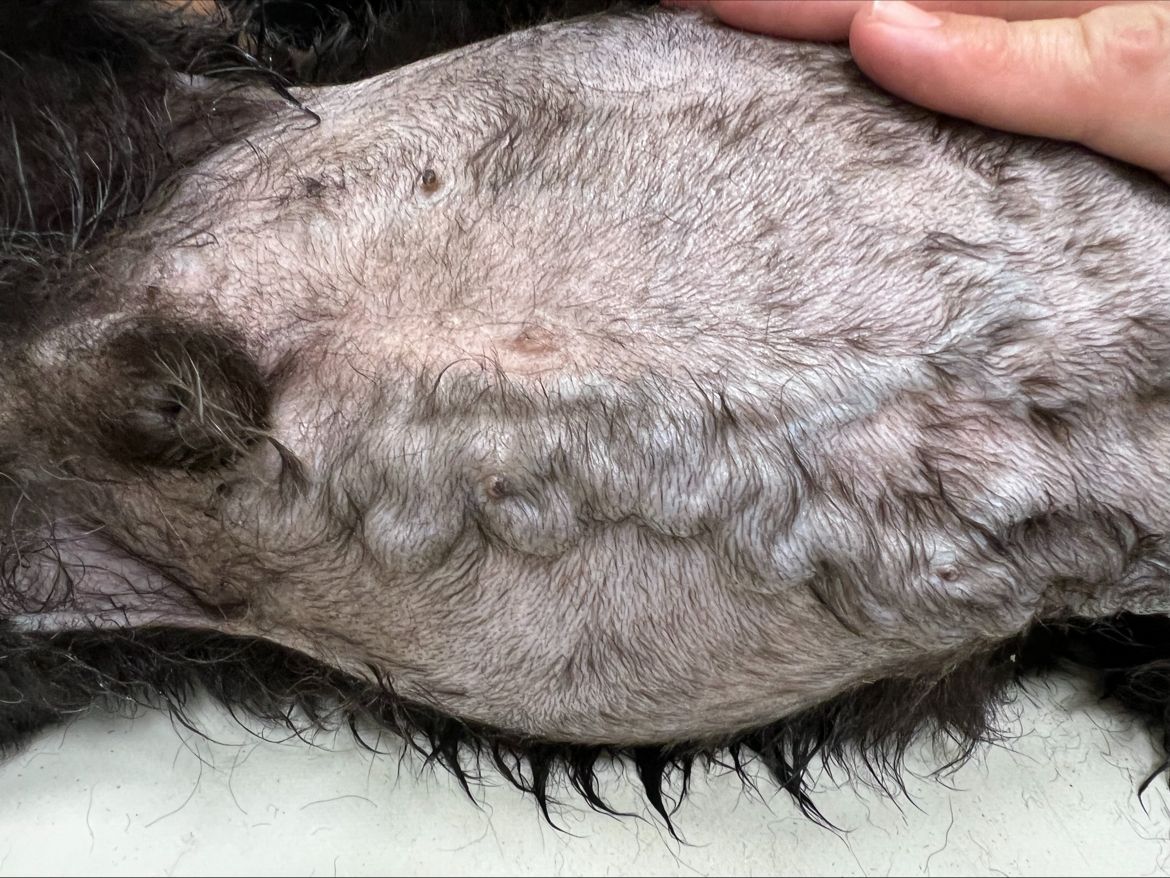

Os presentamos el caso de un cruce de canino macho no castrado de 14 años que acude a consulta con motivo de clara distensión abdominal y severa dilatación de vasos abdominales. Veamos si se corresponde con un tumor en base cardíaca.

2021 – Se observó ecograficamente una masa muy vascularizada en abdomen que no se adheria a ningún órgano.

Se evidencia una masa de grandes dimensiones 10,7 x 8 x 11 cm , con bordes irregulares y captación heterogénea que surge en el abdomen medio, con apariencia sobre el mesentereo y que se extiende hasta abdomen craneal. La masa invade la luz vascular de la vena cava, extendiéndose dicha invasión desde la vena hepática hasta previa bifurcación de las venas iliacas. La aorta abdominal queda envuelta por dicha masa en su recorrido por el abdomen medio. Se identifica vascularización aberrante sobre planos subcutáneos así como hipertrofia de la vena azygos.Masa con infiltración e implicación de estructuras vasculares vitales, así como invasión sobre el riñón derecho, el origen más probable se considera mesentérico dada la centralidad de la misma, sin embargo no es posible descartar origen renal/adrenal, menos probable. Dada la alta infiltración vascular se deberían de considerar neoplasias del tipo endocrinas (paraganglioma/feocromocitoma).

Se observa leve presencia de líquido libre y la masa, que ha aumentado en tamaño, sigue estando muy vascularizada presentand-o alteraciones nivel renal.